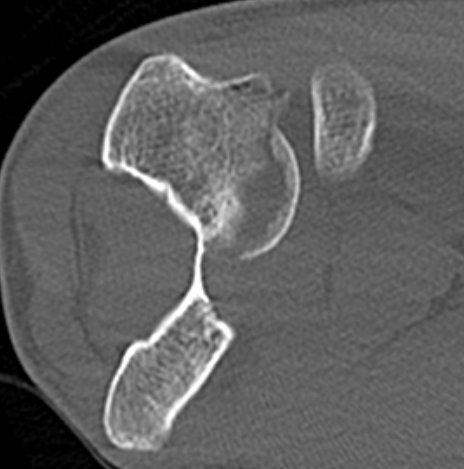

Dubberly Classification

Type I Type Ii Type III

Capitellar fracture

Capitellum + trochlea fracture

In one piece

Double arc sign seen on xray

Capitellum + trochlea fractures

In two separate pieces

Double arc sign on xray